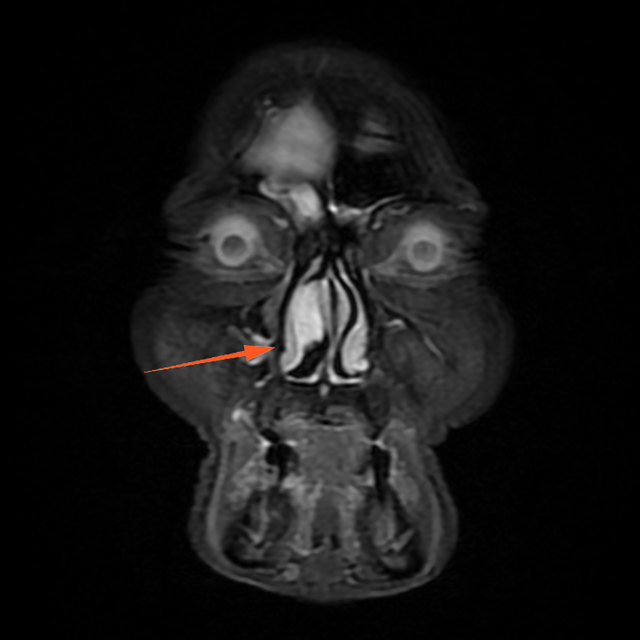

进一步增强MR显示:鼻腔右侧异常信号影,T1等信号,T2等高信号,DWI高信号,增强后周边强化为主。

蒋主任仔细阅读影像学图像,该患者的肿物在T2相有 “脑回征”,但又不典型,鼻窦骨质也没有明显的增生,肿物已经占满整个右侧额窦窦腔,好在患者额窦气化尚可,肿物未越过瞳孔中线,要彻底清除肿物,需要打开额窦,将窦内软组织完全清理干净并磨除基底部部分骨质再烧灼。